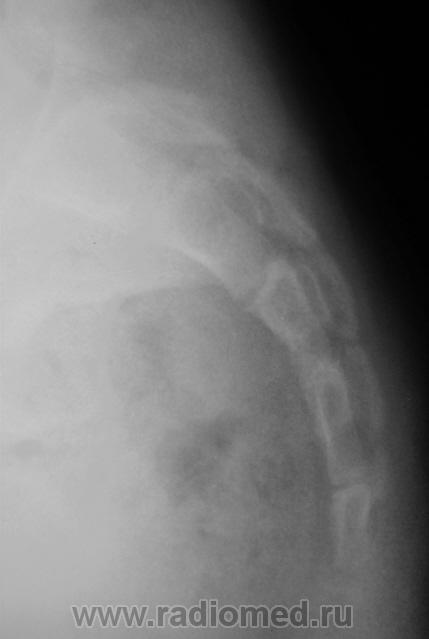

Ребенок направлен хирургом на рентгенографию крестца и копчика, Накануне ребенок упал. Приводится только боковая рентгенограмма, так как рентгенограмма, выполненная в прямой проекции не информативна.

Вопрос. Есть перелом или нет перелома?

Перелома нет

Уважаемый Валентин Львович! Наличия костно-травматических изменений со стороны объекта исследования не выявлено. Кстати, у меня редко получаются такие красивые рентгенограммы крестца и копчика.

Валентин Львович! Мне видится межпозвонковый промежуток. Смещение по ширине отсутствует. Возможно такой вариант развития. Все таки изолированно сломать крестец у ребенка сложно.

Я тоже костно-травматических изменений не вижу.

Согласен с Ермолаевым, это межпозвонковый промежуток.